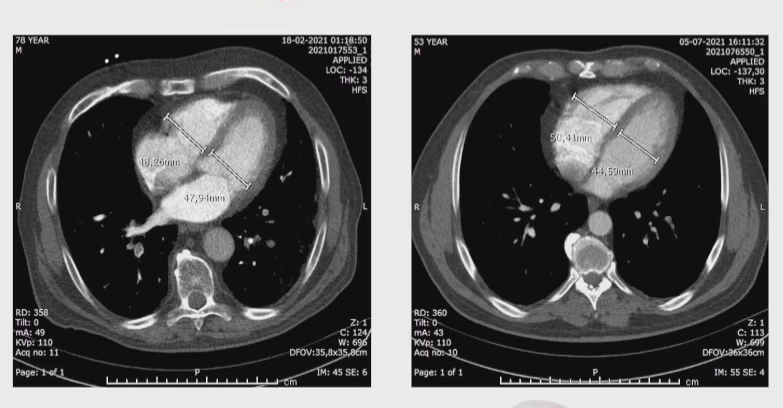

Brain regions in which the microstructure was associated with post-COVID-condition associated symptoms. Image courtesy of Alexander Rau, MD.